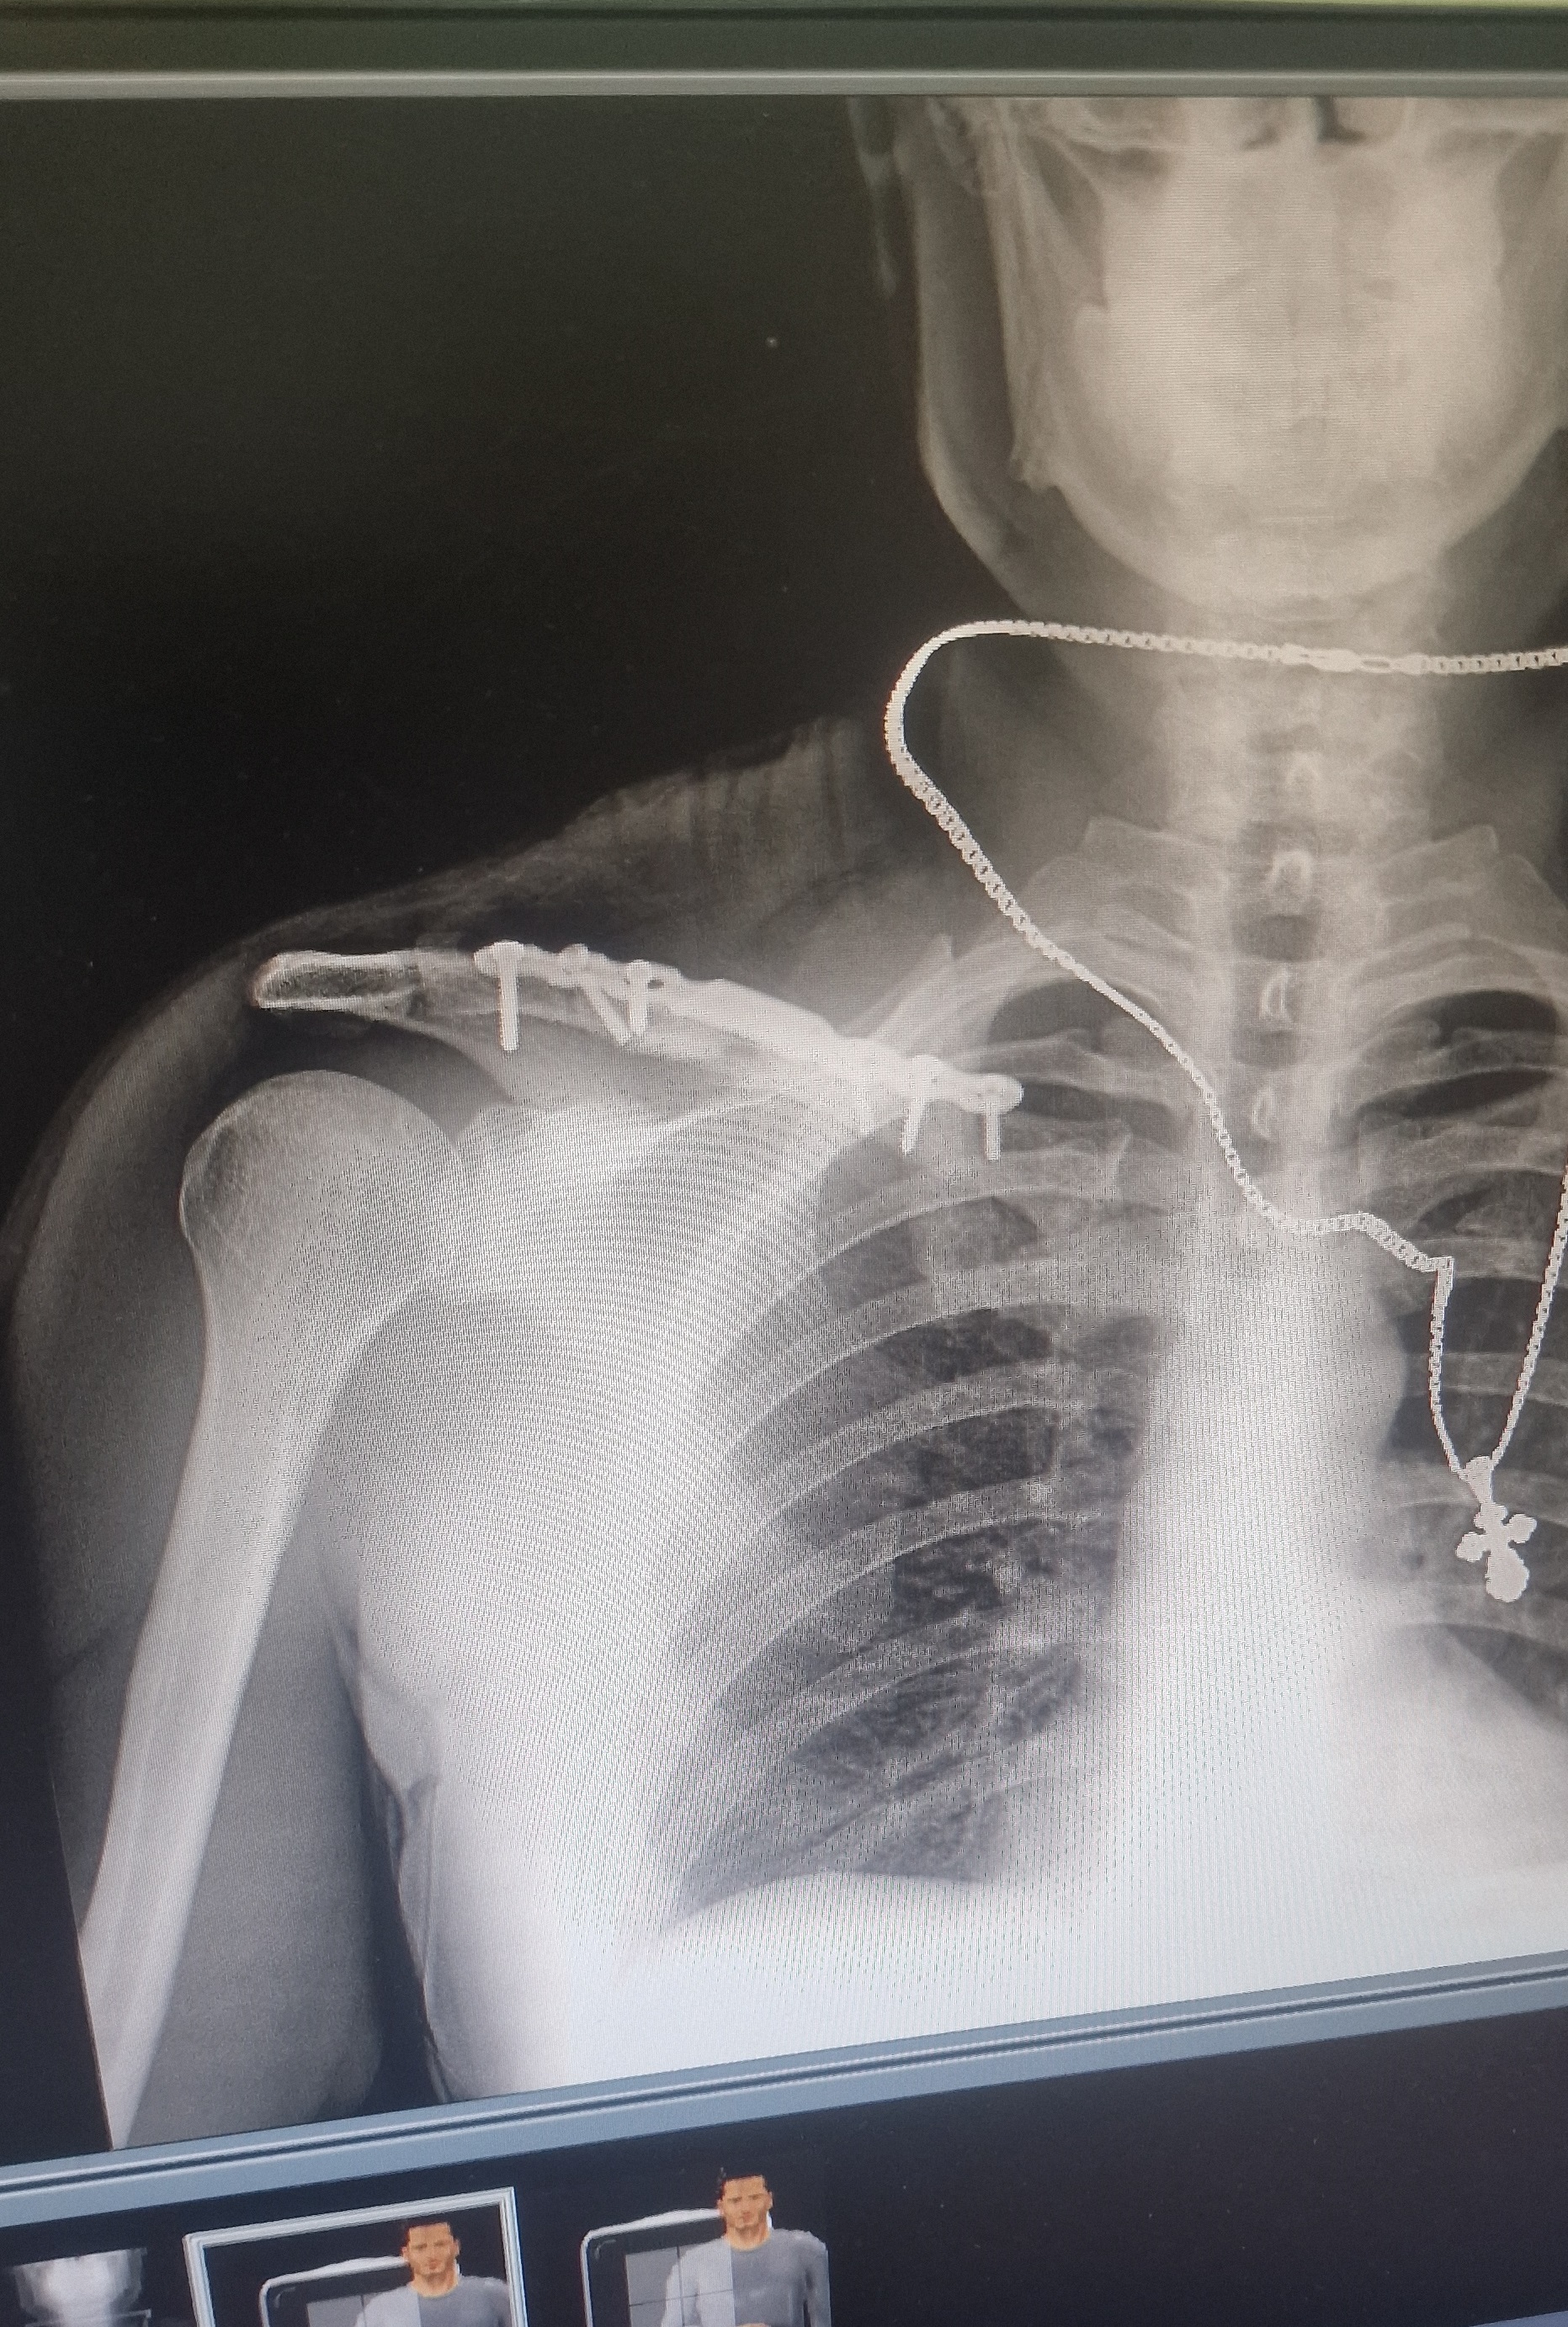

Удаление пластины с ключицы

Итак спустя год и три месяца с момента остеосинтеза ключицы после перелома, я решил, что пластину нужно доставать, так как она доставляла мне дискомфорт.

Начинать следует с похода к травматологу(через терапевта), запись к нему на месяц вперед. Он отправляет на контрольный снимок, если все срослось, одобряет операцию.